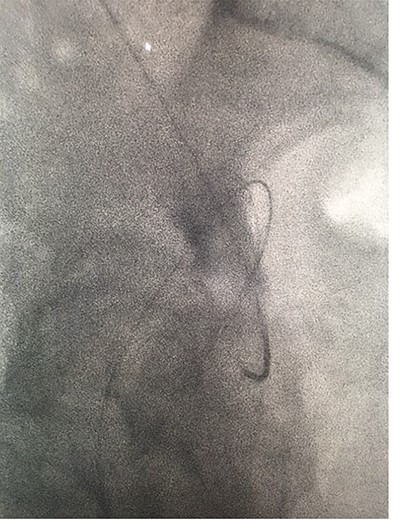

Under conscious sedation, using the previously inserted right percutaneous nephrostomy, antegrade access was achieved into the intrarenal collecting system and then into the proximal ureter. An 8 Fr × 11-cm access sheath was introduced. A guidewire was advanced antegradely through the site of ureteric transection and coiled in a position adjacent to the position of the guidewire that had been inserted retrogradely. A Gooseneck snare catheter was then passed over the guidewire and the snare was inserted (Figs 4 and 5). Under fluoroscopic guidance, the retrograde wire was retrieved and brought externally via the nephrostomy site, achieving through-and-through wire access (Figs 6 and 7).

Fluoroscopic images showing the retrograde wire successfully retrieved and brought externally via the nephrostomy site, achieving through-and-through wire access.